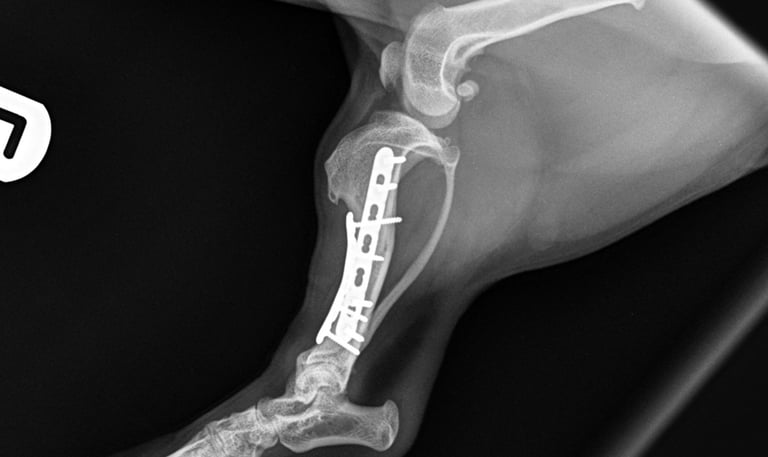

Case 1 - Charlie

Ilial wing fracture – DSH, 2y, female